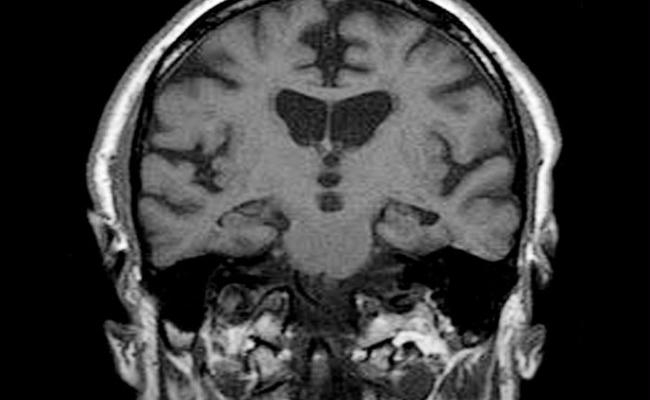

लॉस एंजिलिस : मस्तिष्क के एमआरआई स्कैन से पता लगाया जा सकेगा कि व्यक्ति को अगले तीन वर्ष में डिमेंशिया होने की आशंका तो नहीं है. इसका मतलब है कि विकार के लक्षण नजर आने से पहले ही इसके जोखिम का अनुमान लगाया जा सकता है.

अमेरिका में वाशिंगटन यूनिवर्सिटी और कैलिफोर्निया यूनिवर्सिटी के शोधकर्ताओं ने अध्ययन में डिमेंशिया का अनुमान लगाने के लिए मैग्नेटिक रेसोनेंस इमेजिंग (एमआरआई) का इस्तेमाल किया. यह अनुमान 89 फीसदी सटीक रहा.

उन्होंने कहा, ‘हमने बताया कि केवल एक एमआरआई स्कैन से 2.6 वर्ष पहले ही डिमेंशिया के जोखिम का पता लगाया जा सकता है. इससे चिकित्सक समयपूर्व अपने मरीजों को सलाह दे सकेंगे और उनकी देखरेख कर सकेंगे.’